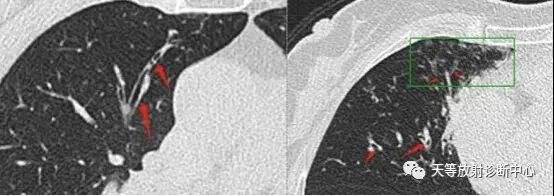

图7马赛克,低密度区空气潴留,高密度血流再分配,支气管扩张,支气管壁增厚。

图8缩窄性毛细支气管炎,双肺中马赛克样灌注的不均匀区域(箭头所示)。外科肺活检得到的病理切片在低倍镜(×40)下显示,细支气管胶原类纤维引起膜性细支气管腔的狭窄(箭头所示),显示上皮细胞和黏膜肌层间固有层的纤维性增厚(箭头所示)。